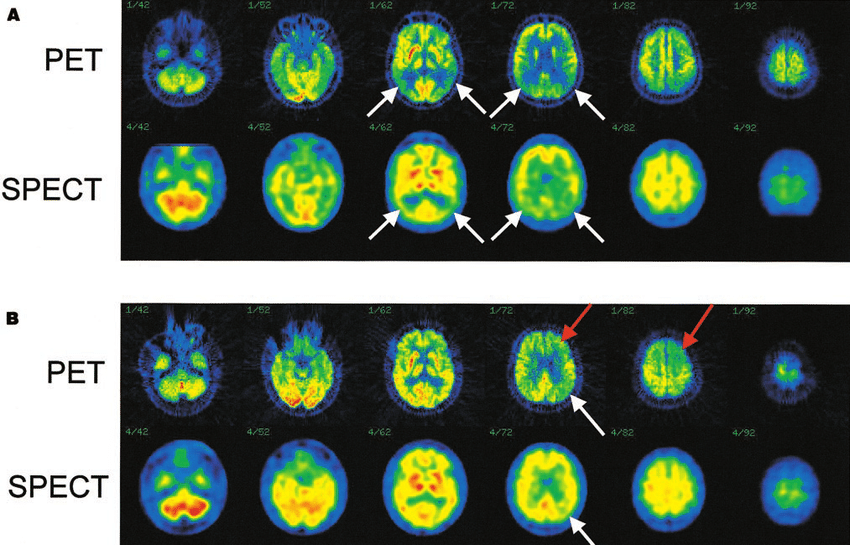

Techniques like PET scans (Positron Emission Tomography) and SPECT scans allow doctors to see metabolic activity inside the body. Instead of simply spotting a lump, doctors can identify whether cells are behaving like cancer long before tumours become obvious.

This is why early cancer detection has improved so dramatically in the last few decades. A PET scan doesn’t just show structure. It shows function. It tells doctors: Is this cancer active? Is it spreading? Is treatment working? That one ability has saved millions of lives.